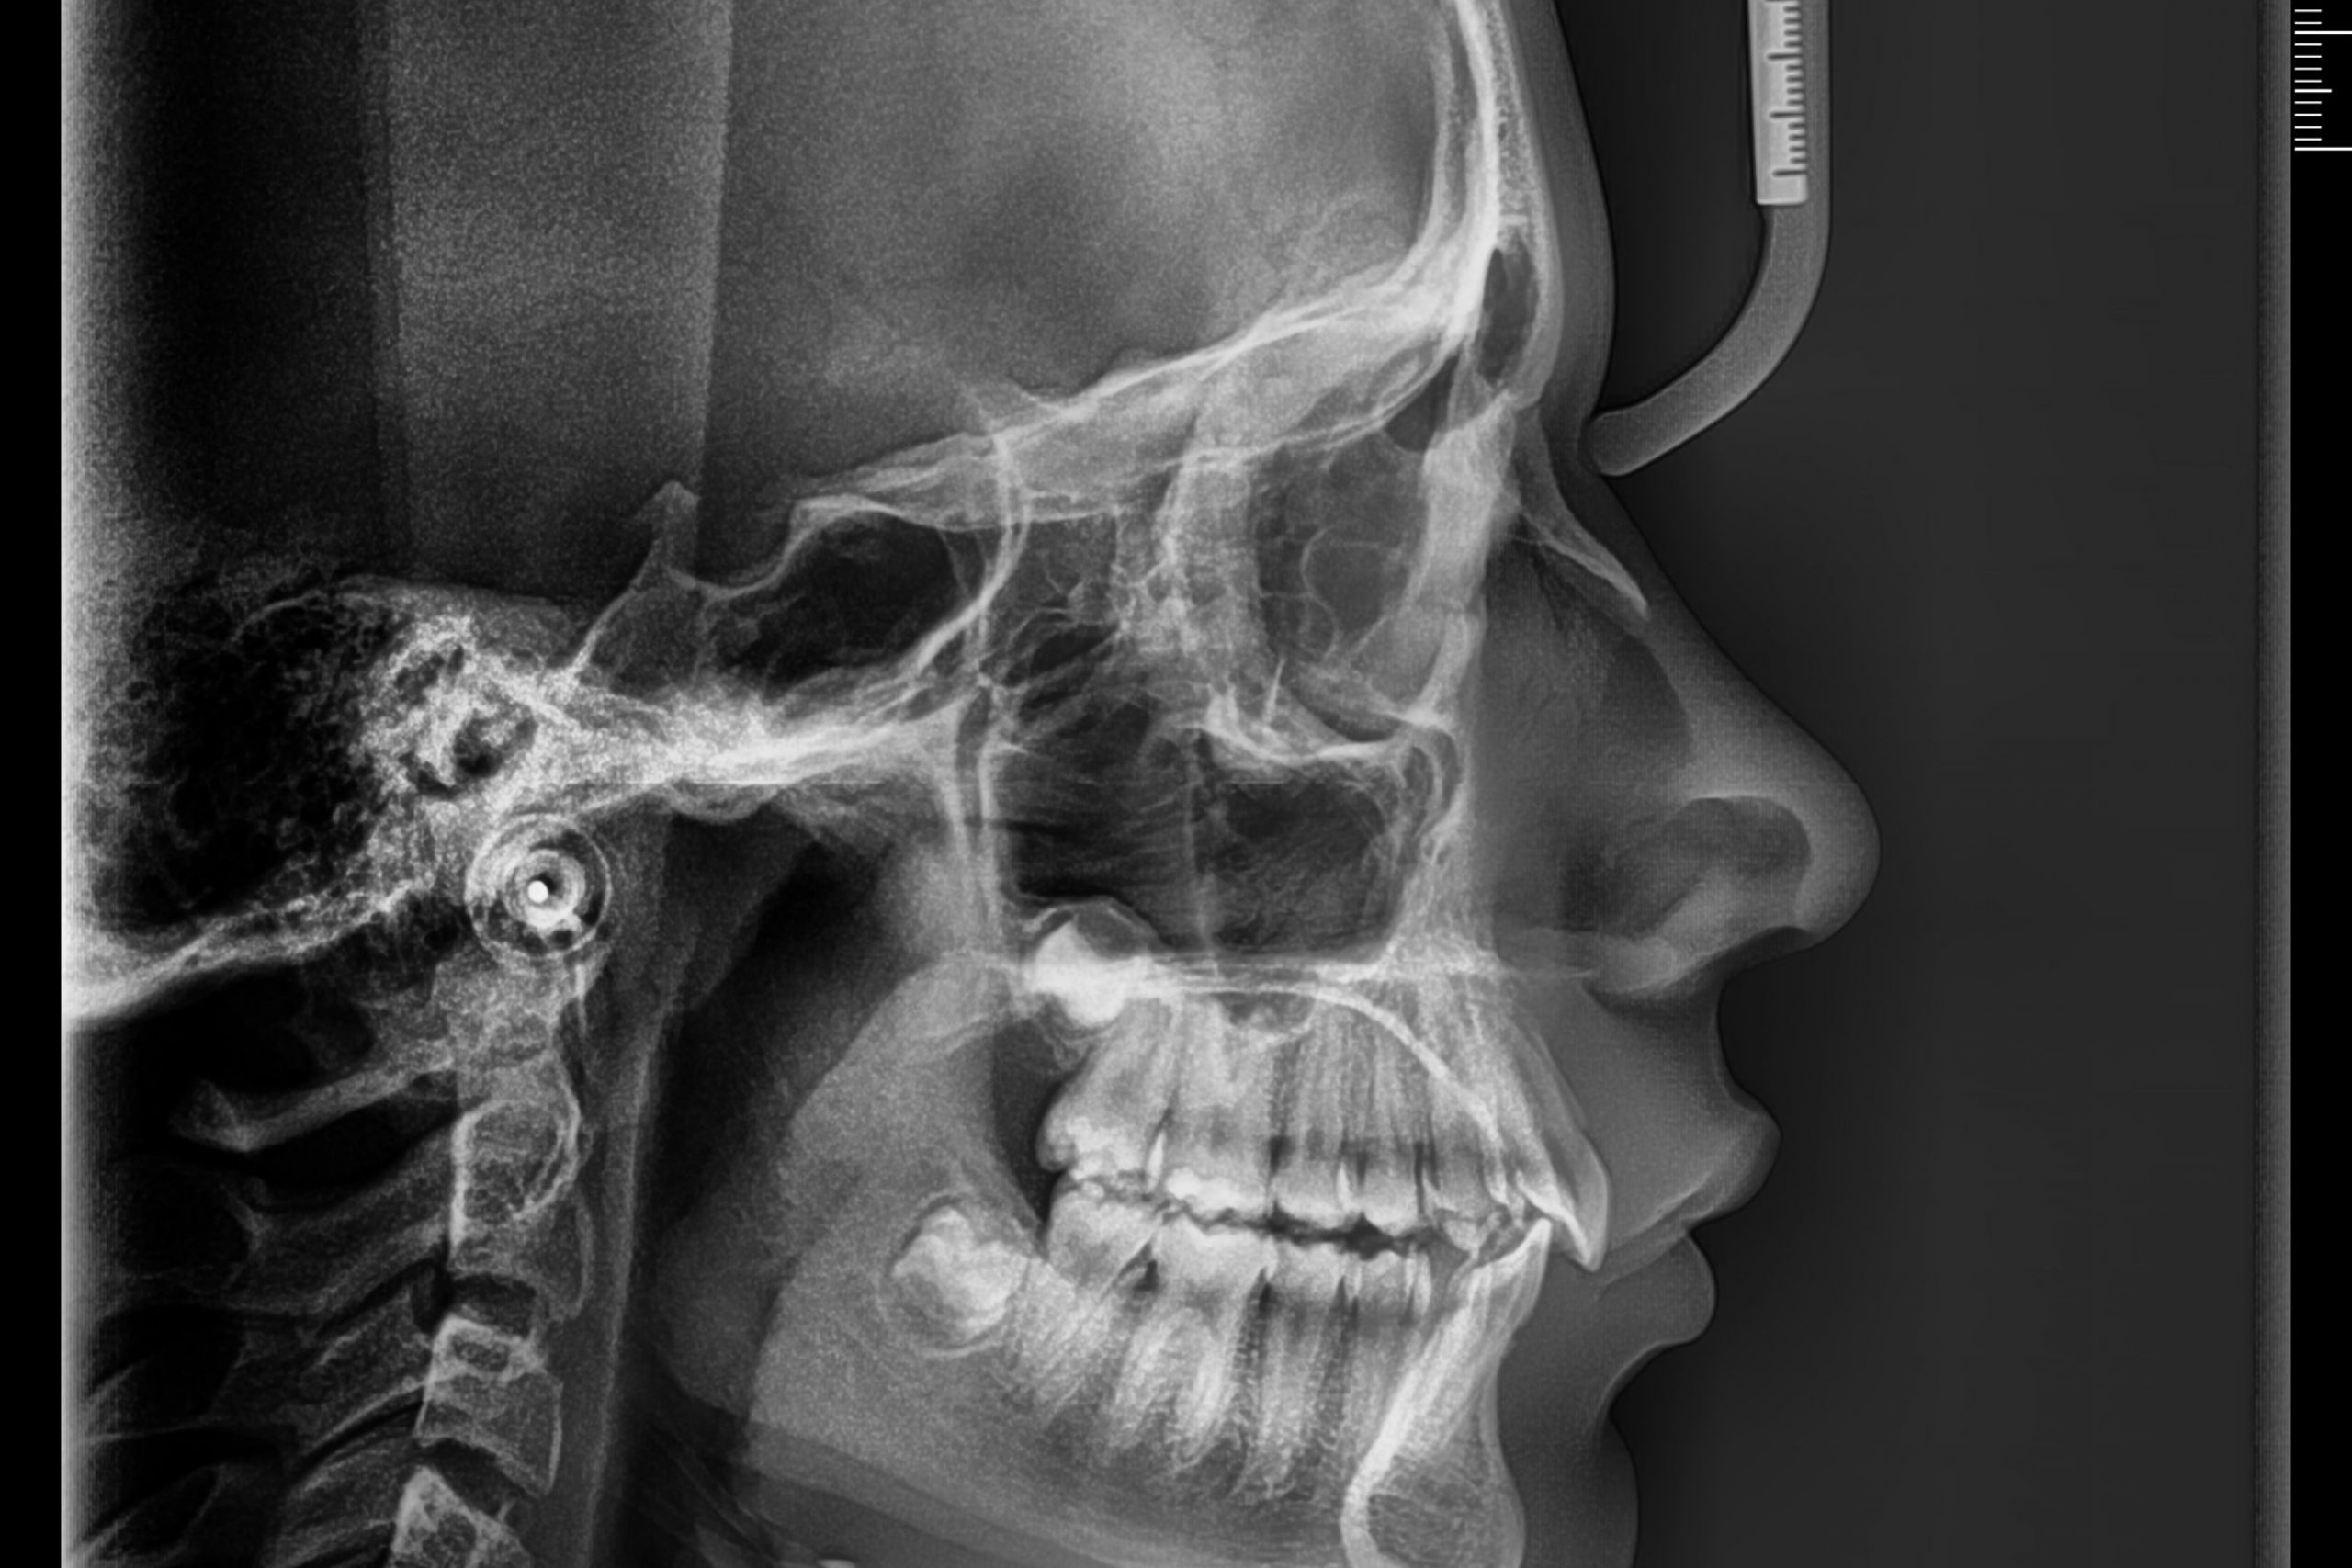

Ortodoncia y Ortopedia Dentofacial

Especialistas con dedicación exclusiva, estudio cráneo-métrico y fotográfico.